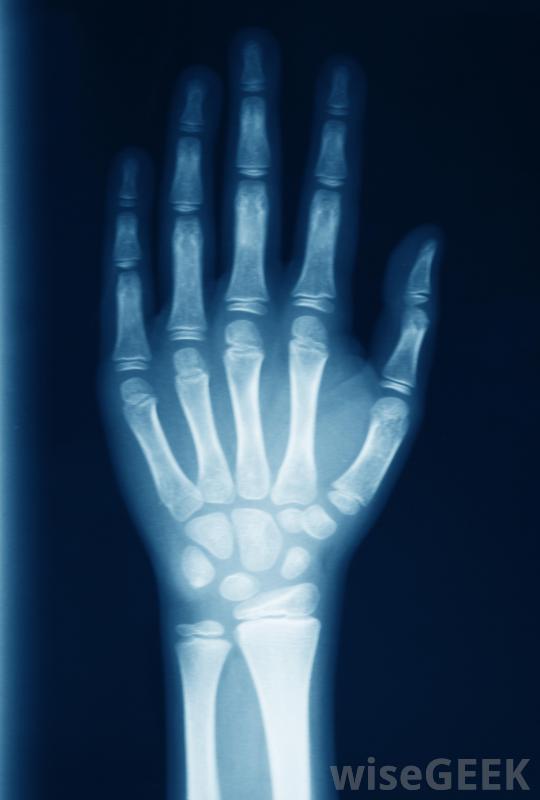

用键盘打字会对手腕造成困难,可能会加重腕管问题并导致手指麻木腕管综合征是导致手指麻木的最常见原因之一,它是一种由长期重复运动引起的病症,尤其是当手腕或手的位置不正确时,使用电脑的人最容易患腕管,大多数情况下一个或多个手指会变得麻木,然后手和手腕会疼痛,有时还会肿胀治疗方法包括戴上特制的支具,偶尔还要做手术。

桡神经病变会导致手腕出现问题,也会导致手部部分麻木。

手腕受伤可能导致手指麻木。